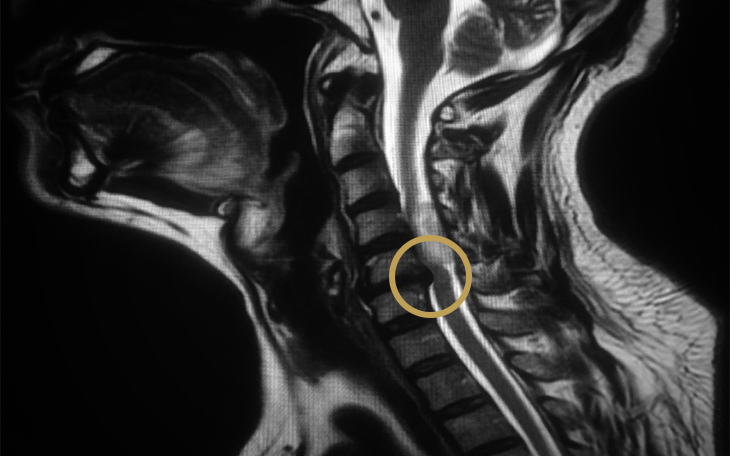

Ein einfaches Röntgenbild der Wirbelsäule zeigt nur die Knochenstruktur, nicht jedoch die Bandscheiben oder Nerven. Für eine exakte Diagnose wird daher ein MRT (Magnetresonanztomographie) empfohlen. Es ist nicht-invasiv und zeigt die betroffene Bandscheibe deutlich. Vor der Verfügbarkeit des MRT wurden CTs oder Myelogramme genutzt. Bei Patienten mit Herzschrittmachern, die kein MRT machen dürfen, müssen diese Verfahren weiterhin eingesetzt werden.

Konventionelle Röntgenaufnahmen sind zur Ersteinschätzung wichtig. Bei instabilen oder nicht verschobenen Frakturen kann eine CT nötig sein. Ein MRT ist essenziell zur Beurteilung von Rückenmark, Bändern und Weichteilen und sollte möglichst vor einem operativen Eingriff erfolgen.

• MRT (Magnetresonanztomographie): Zeigt Weichteilverletzungen, Nervenkompression oder Rückenmarkschäden. Sollte vor jeder Reposition (manuell oder operativ) erfolgen, wenn der Patient neurologisch unauffällig ist.

Die Diagnose basiert auf einer gründlichen Anamnese und körperlichen Untersuchung. Röntgenbilder können Arthrose zeigen, liefern jedoch keine ausreichenden Informationen zur Rückenmarkskompression. Eine MRT ist das Mittel der Wahl zur Beurteilung des Ausmaßes der Stenose. Bei Patienten mit Herzschrittmacher oder MRT-Kontraindikationen sind CT-Myelogramme eine Alternative.